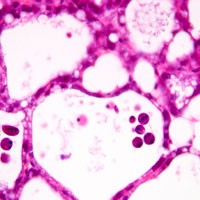

A novel mechanism of cell death that occurs in mammalian organisms has been revealed by researchers at the University of Cambridge. Billions of damaged or superfluous cells die in our bodies every day. It is thought that most cell death occurs by a process called apoptosis, in which biochemical events lead to cell changes and death. However, during the course of Peter Kreuzaler's PhD research at the Department of Pathology, the Cambridge team have shown that cells in the breast die following lactation by a process that involves lysosomes - organelles which digest and recycle cellular components. As the mammary gland regresses, enzymes called cathepsins leak out of the lysosomes into the cell and induce cell death. This is the first time that this type of cell death has been shown to occur in a healthy mammal: the original work was done in vivo in mice. Additionally, the protein Stat3, which is present in high levels in cancers that have poor prognosis, plays a significant role in lysosomal-mediated programmed cell death as it induces high levels of cathepsins while suppressing cathepsin inhibitors.